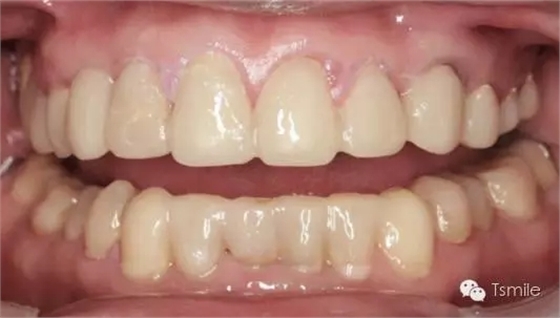

例如面對(duì)一個(gè)牙列重度磨耗的美學(xué)修復(fù)患者,我們首先根據(jù)患者主訴和美學(xué)檢查形成美學(xué)設(shè)計(jì),然后通過(guò)數(shù)碼圖像表達(dá)美學(xué)設(shè)計(jì)思想,制作診斷蠟型,口內(nèi)制作診斷飾面,更加真實(shí)地表達(dá)美學(xué)設(shè)計(jì)。根據(jù)患者的要求和口內(nèi)試戴情況調(diào)改診斷飾面,最終確定美學(xué)修復(fù)設(shè)計(jì),即最終修復(fù)體的各種美學(xué)參數(shù)。接下來(lái)就是美學(xué)實(shí)現(xiàn)過(guò)程,在診斷飾面上進(jìn)行精確地牙體預(yù)備,制取印模和工作模型,技師按照最終診斷飾面的形態(tài)、大小和排列制作最終美學(xué)修復(fù)體,最后完成修復(fù)體粘接。

前兩個(gè)美學(xué)分析和美學(xué)表達(dá)過(guò)程已經(jīng)確定了患者滿意的最終的美學(xué)修復(fù)設(shè)計(jì),也就是已經(jīng)確定了最終修復(fù)體的形態(tài)、大小、排列、牙齦曲線等各種美學(xué)參數(shù),美學(xué)實(shí)現(xiàn)就是復(fù)制前面已經(jīng)確定的美學(xué)設(shè)計(jì)的過(guò)程,包括牙體預(yù)備、印模制取、修復(fù)體制作、修復(fù)體試戴粘接等過(guò)程。